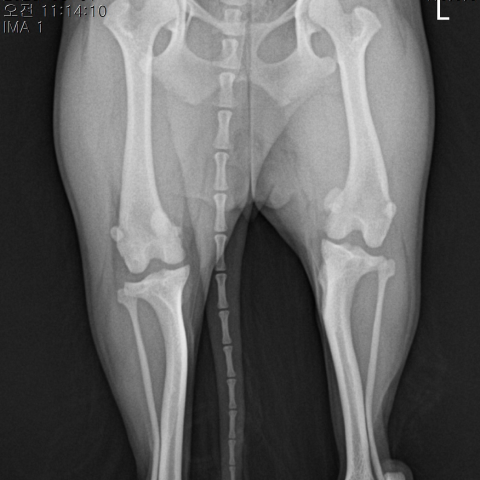

½½°³°ñ Å»±¸ ¼ö¼ú Àü